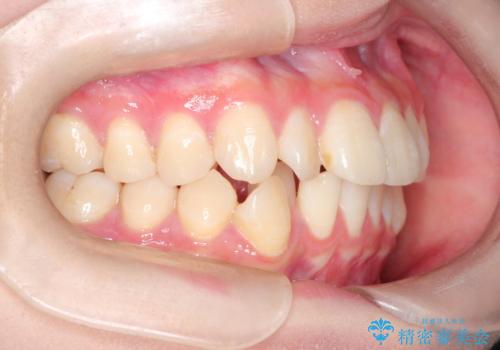

インビザラインによる矯正治療(非抜歯) 前歯の捻れとガタつきの改善

- 上下の前歯に捻れ(捻転)とガタつき(叢生)が見られます。

上の2番目の前歯の捻れに関しては、元々歯の大きさが小さい歯であるため、マウスピースにて力がかかりにくく、捻転の改善が一般的に難しくなりがちです。

下の犬歯に関しても捻れと傾き、ガタつきが大きく、歯根の長さも相まって移動の難易度が高くなりがちです。

インビザラインのそうした特色を踏まえた上で、それらをリカバーできるように治療方式の調整を十分に行い、治療を進めました。

マウスピース枚数 初回33枚 +追加22枚 +追加31枚

概ね2年で治療完了しました。

マウスピース矯正の特性として動かすのが難しい歯を含むケースでしたが、当院独自の工夫を随所に盛り込み、狙い通りの治療結果が得られました。